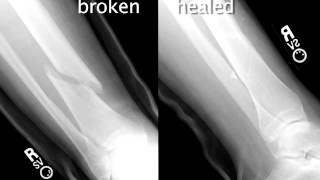

The STEM Concept Videos are designed to help students learn a pivotal concept in science, technology, engineering, and/or mathematics (STEM). These ideas are the building blocks of many engineering curricula, and learning them will help students master more difficult material. The STEM Concept Videos were produced by the Teaching and Learning Lab (TLL) at MIT for the Singapore University of Technology and Design (SUTD).